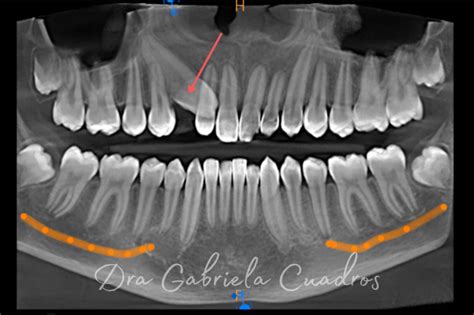

Radiografía que muestra un colmillo retenido en el paladar.

Muchos adultos aún conservan los dientes de leche y se preguntan si los definitivos les saldrán alguna vez, si carecen de ellos, si es posible una ortodoncia o por qué esto es así. Lo esencial es saber cuál es la razón y cómo solucionarla. Lo primero que hay que hacer es realizar una radiografía (ortopantomografía) para ver qué está pasando. En ella veremos si detrás del diente de leche hay o no un diente definitivo. Dependiendo de si existe o no estaremos ante una situación u otra.

Por un lado puede deberse a que los dientes definitivos estén aún por salir, suelen ser premolares y, sobre todo, en caninos superiores. El motivo principal por el que puede que no hayan salido, suele ser la falta de espacio. Ésta causa muchas veces está relacionada con un componente hereditario, encontrándose algún padre, abuelo o tío, en la misma situación.